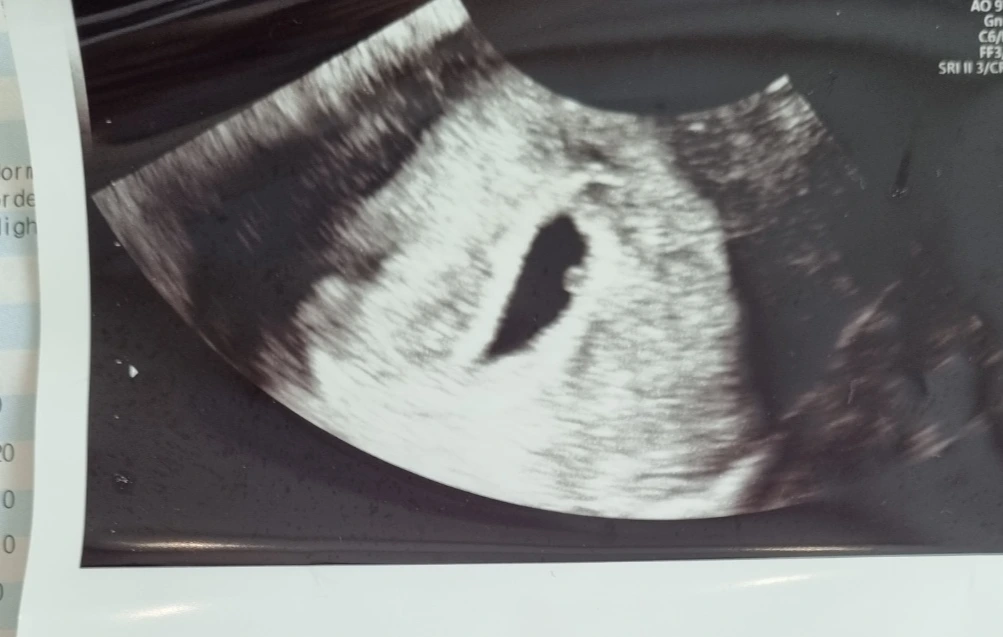

처음 만난 아기의 모습은 작은 점에 불과했다

5주 차 1일.

아기가 생긴 걸 알고서 처음으로 초음파 검사를 통해 아기를 만난 날이다. 조그맣게 자리 잡은 아기집 안에 더 조그마한 점 하나만이 보였다. 이 조그마한 점이 생기기 위해, 수많은 우연과 인연이 켜켜이 겹쳐야만 했다. 아내와 프랑스로 신혼여행을 떠났기 때문에, 결혼하기로 마음을 먹고 대청호가 지척인 레스토랑에서 상견례를 했기 때문에, 선배의 소개로 처음으로 아내와 서울 강서구청 먹자골목에서 술을 마셨기 때문에, 시골에서 근무하다 별안간 인천으로 올라왔기 때문에, 더 원초적으로는 나와 아내가 각자 엄마의 자궁에서 나와 이 넓은 세상에 태어나, 초음파에서 보이는 이 작고 검은 점이 생겨날 순간을 위해서 예비되었기에 가능했다.

작은 점은 그렇게 모든 순간들이 겹쳐나 시작돼 우리가 발 딛고 서 있는 지구에 도달했다. 역사상 가장 철학적인 사진이라는 위 사진은 1990년 2월 14일 보이저 1호가 촬영한 지구의 모습이다. 61억 킬로미터 떨어진 우주에서 찍은 지구는 말 그대로 창백한 푸른 점에 불과하다. 아기를 찍은 초음파 사진과 지구를 찍은 위성사진은 닮아있다. 광활한 우주 속의 창백한 푸른 점에 불과한 지구에서 아내의 뱃속에 자리 잡은 작은 점을 만났다는 건, 기적이라는 단어로밖에 설명되지 않는다. 이 기적은 이제 작은 점에서 생명의 모습을 갖추고 곧 세상의 빛을 받을 날을 앞두고 있다.